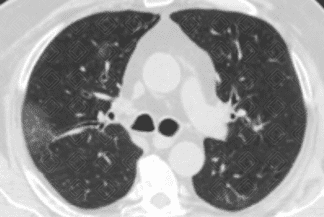

Descrição das figuras 1, 2 e 3: Tomografia computadorizada de tórax no momento da admissão. Esparsas opacidades em vidro fosco bilaterais, com envolvimento de mais de um lobo pulmonar e com distribuição predominantemente periférica. Em associação às áreas em vidro fosco, pode ocorrer ainda espessamento dos septos interlobulares, caracterizando o padrão de pavimentação em mosaico.

• Opacidades em vidro fosco, bilaterais, acometendo a maioria dos lobos pulmonares (acometimento multilobar), assimétricas e com predomínio na periferia dos pulmões;

• Em associação às áreas em vidro fosco, pode coexistir o espessamento dos septos interlobulares, caracterizando o padrão de pavimentação em mosaico;